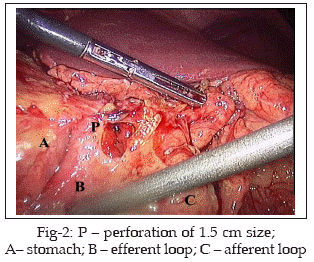

The patient was a 45-year old male presenting with features of acute abdomen and peritonitis. He had undergone laparotomy for peptic ulcer disease 20 years ago; details were not known. On examination, he had tachycardia; hypotension; dehydration; tachypnea; oliguria; abdomen was rigid; rebound tenderness present; absent bowel sounds and a midline scar almost three inches below the xiphisternum was seen. The lab values showed anemia; mildly deranged electrolytes; elevated urea levels; liver function was normal including prothrombin time. On laparoscopy, there was extensive soiling of the peritoneal cavity with inflammatory flakes and bilious fluid (Fig-1). This was sucked out and a thorough saline wash was given. The small and large bowels were carefully inspected and found to be normal. On the anterior surface of the stomach, an isoperistaltic GJ anastomosis was seen. A 1.5cm perforation was found in the efferent loop of the jejunum at the anastomotic site (Fig-2). A pedicled strip of omentum was mobilized up to the perforation site and anchored with interrupted 20 vicryl intracorporeal sutures (Fig-3). The stitches were placed all around the perforation by taking seromuscular bites on the bowel and the omentum. Five such sutures were necessary to complete the omental patch. Air was pushed forcibly through the nasogastric tube and the sutured area was inspected for any leak by checking for air bubbles in a pool of saline. The postoperative period was uneventful. The nasogastric tube was removed on the 3rd postoperative day (POD), oral liquids were allowed on the 4th POD, patient started taking soft diet on the 5th POD, the drainage tube was removed after USG showed no intra-abdominal collection on the 6th POD and the patient was discharged on 7th POD.